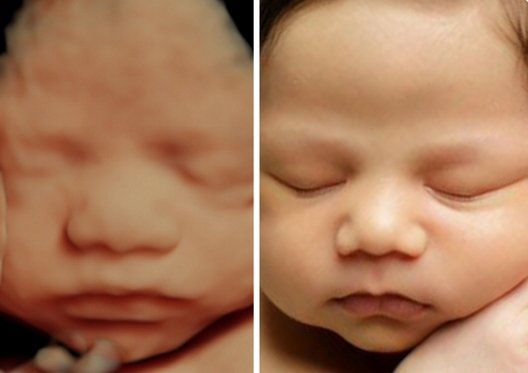

We provide quick and accurate Emergency Sonography, X-Ray, and Doppler services for immediate diagnosis.